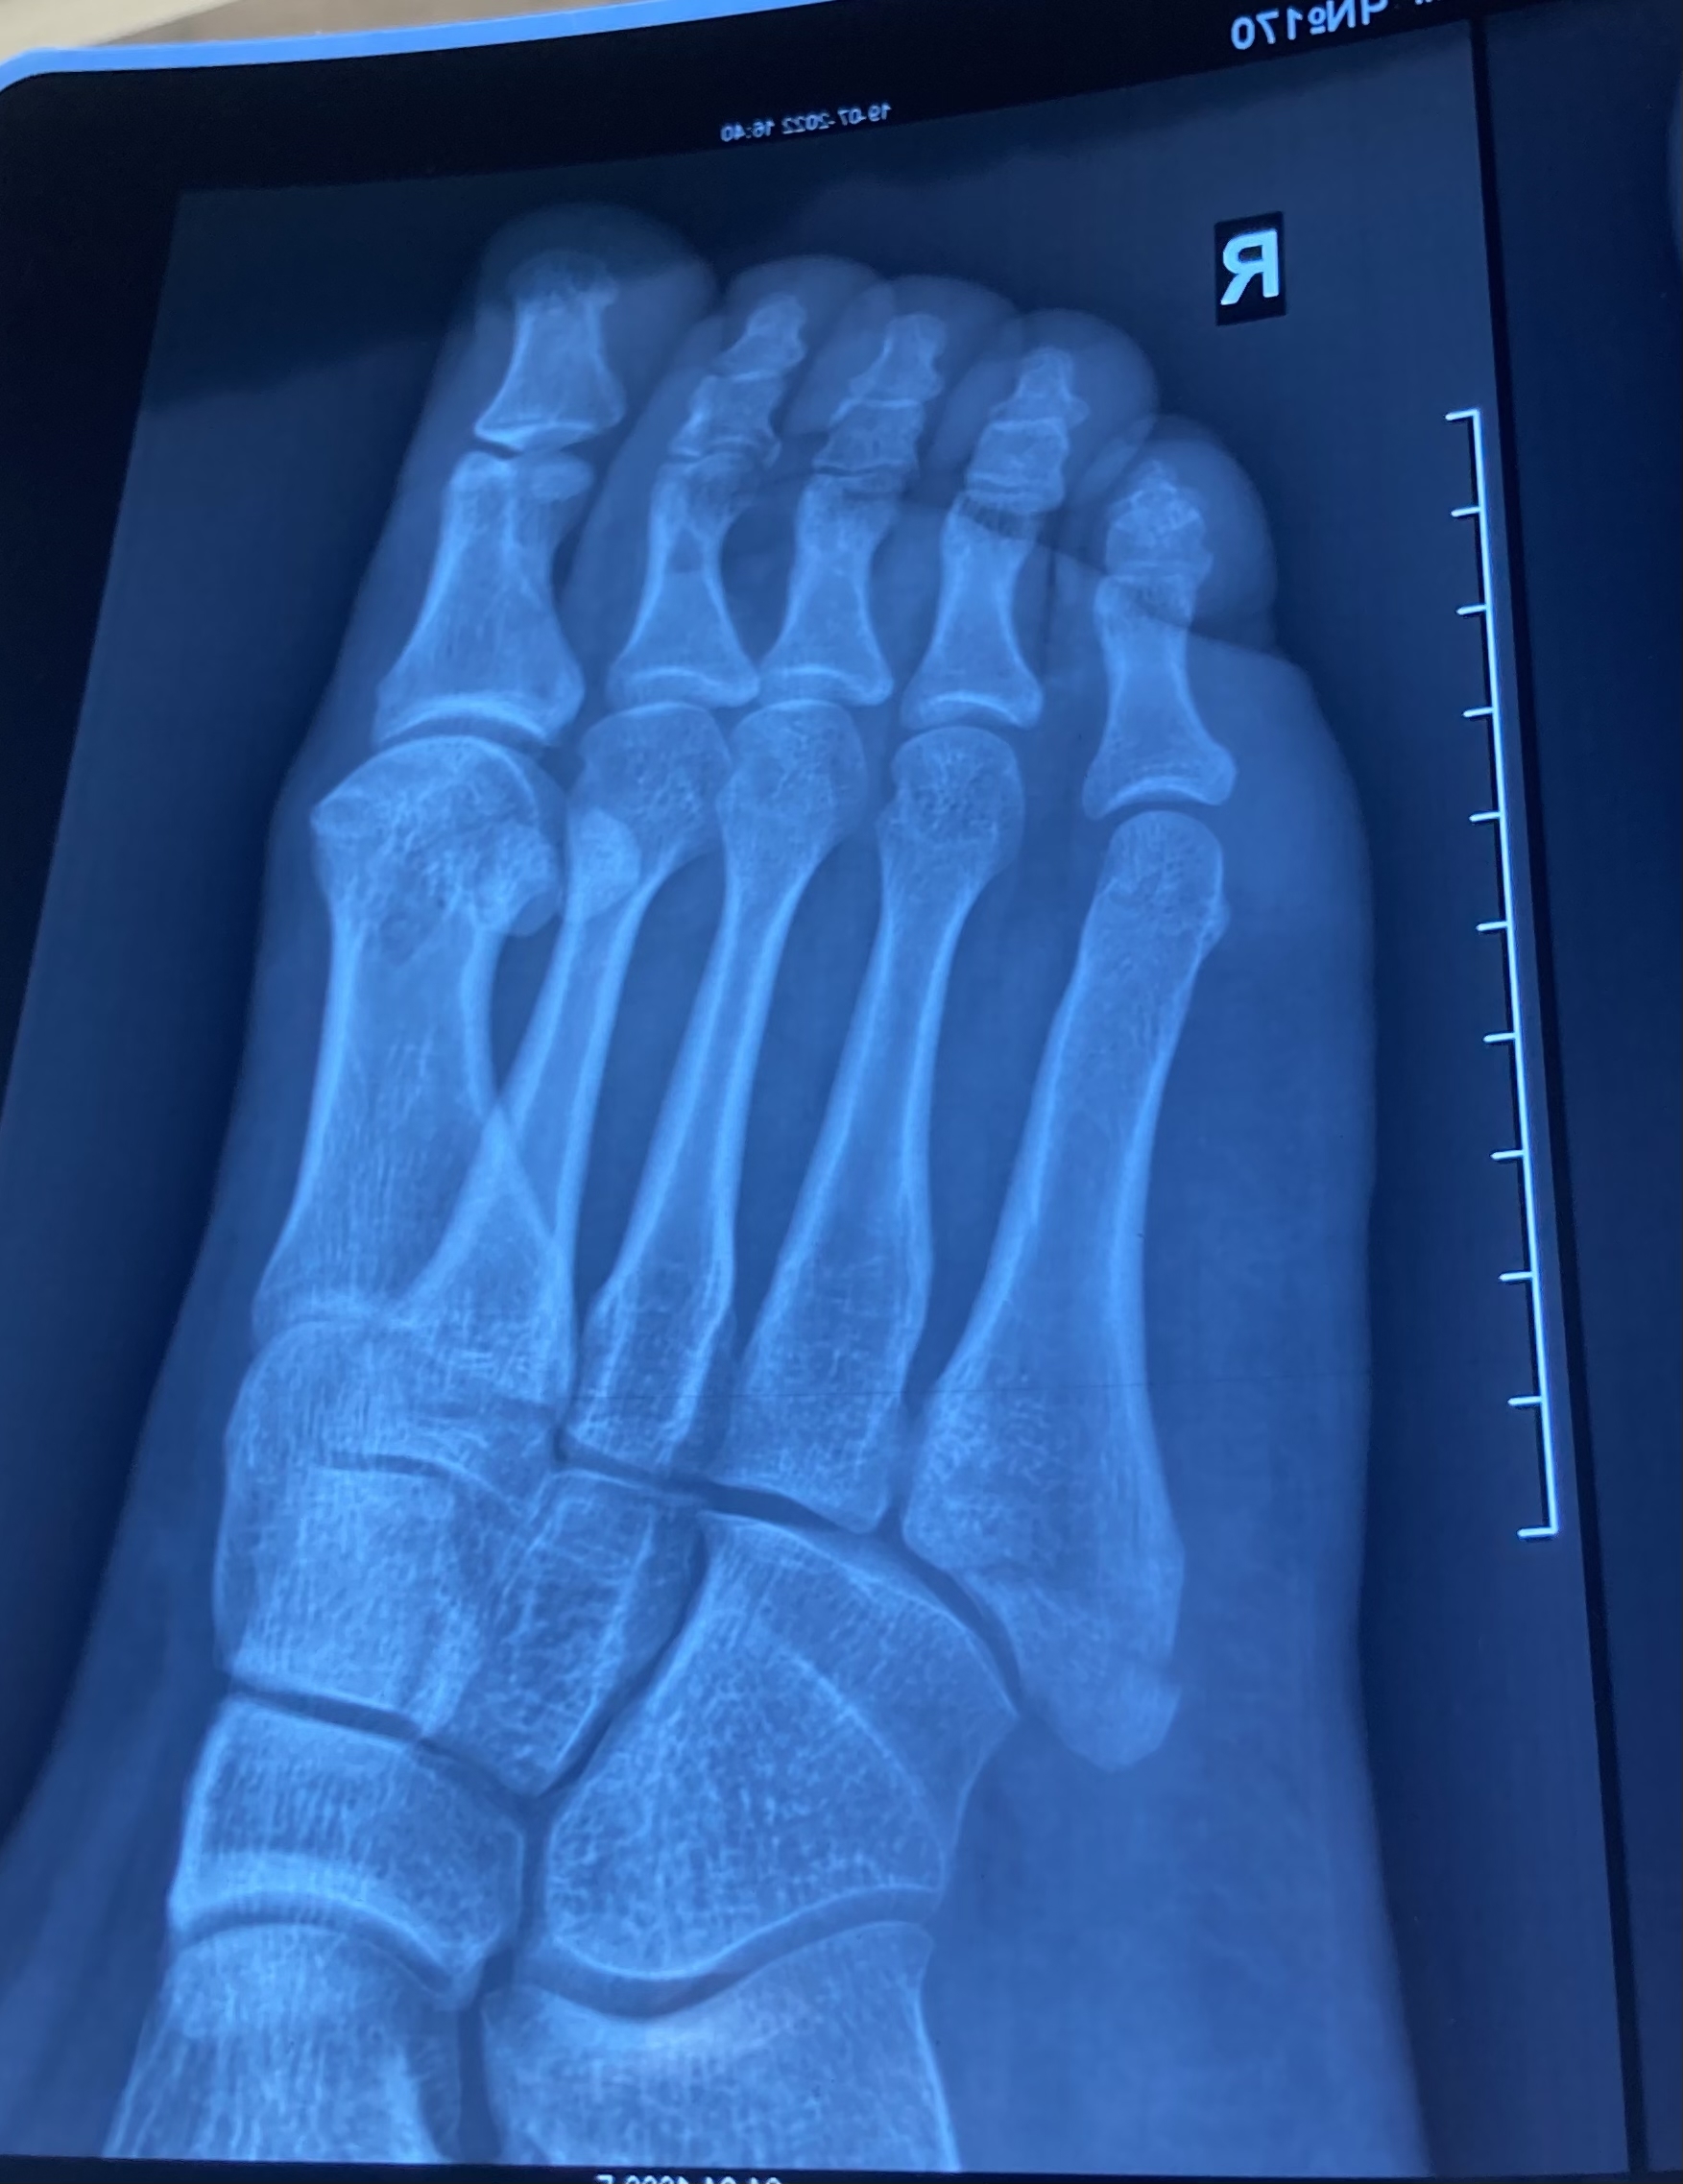

У всех тут море подобных историй, моя не исключение. Упала с лестницы, на ногу наступить не могла. Сразу поехали в травмпункт, доктор ногу осмотрел, постучал по пятке, покрутил и сказал, что это растяжение. Скинул ссылку для покупки ортеза за 11к и отправил домой. 10 дней сидела дома, нога была сине-жёлто-фиолетового цвета, опухшая. Наступать осторожно пробовала, больно. В итоге решила, что что-то тут не так (да да, только тогда), пошла поковыляла и рентген платно сделала. Закономерный итог - перелом пятой плюсневой кости. Повезло, что без смещения. При повторном посещении травмпункта даже гипсовать не захотели, сказали «Ой, да не надо вам, неудобно же, наступать нельзя, мыться нельзя. У нас наоборот все от гипса отказываются». Настояла, загипсовали, а доктор из всех рекомендаций только сказал, что через пару дней можно прийти и платно пластиковый гипс наложить.